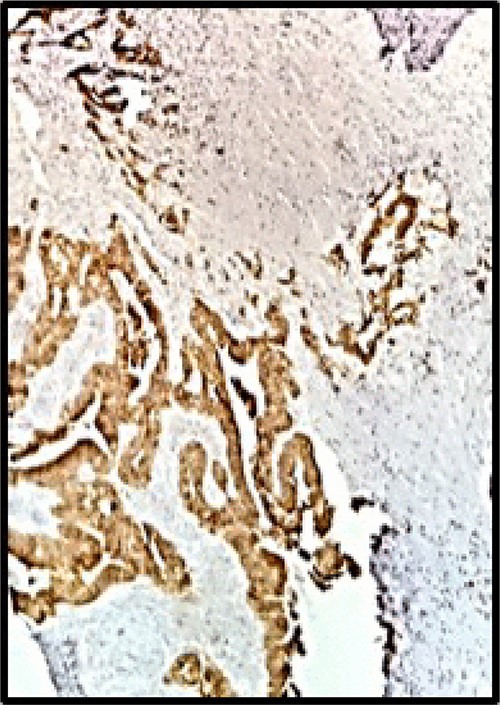

Postoperative pathology confirmed that the right ovarian parenchyma had an infiltration by carcinoma of the intestinal type, with corpus luteum and endometriosis; and material sent as a ganglion corresponds to a giant cellular reaction by foreign material. Immunohistochemistry: CK7, CA 125 and WT1 were negative (Fig. 3), CK20 was positive, intense and diffuse in metastatic proliferation (Fig. 4). The histopathologic confirmed a Krukenberg tumor of the ovary and immune profile favored a metastatic gastrointestinal carcinoma.

Immunohistochemistry: CK20 was positive, intense and diffuse (HE 40X).